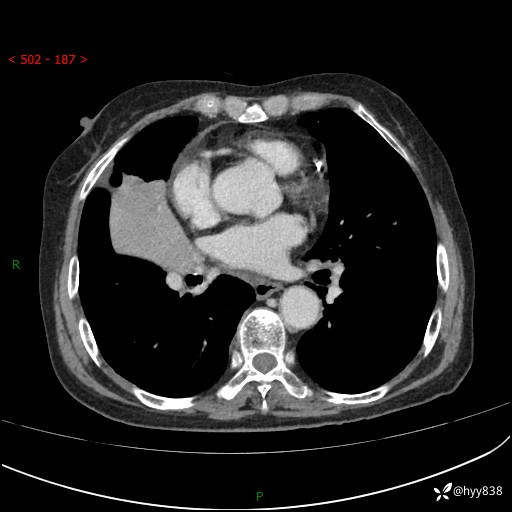

胸部CT增强(外院平扫)